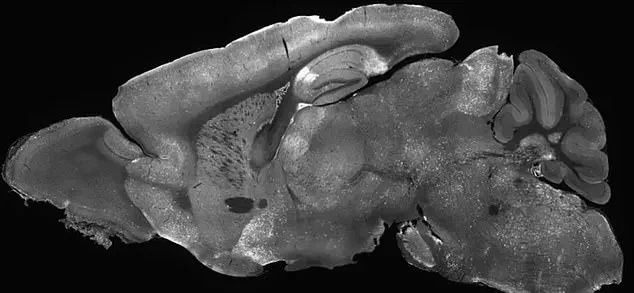

The therapy involved injecting the modified adenoviruses into the mice’s cerebral ventricles, the fluid-filled cavities in the brain, using a needle inserted past the eye.

This technique, though invasive, demonstrated the feasibility of targeting specific brain regions with precision.